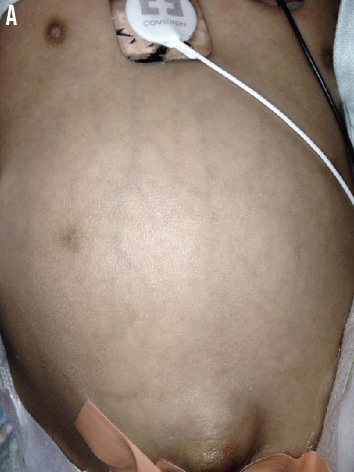

Babu S. Bangaru, MD; Susana Rapaport, MD; Asri Yuliati, MD

A 14-year-old girl presented to a hospital with concern for progressively worsening diffuse abdominal pain.

08/27/2015